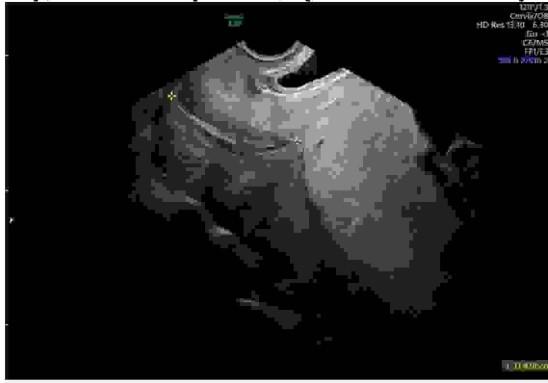

Pacjentka lat 27, ciąża II, tydz: 27, przyjęta do szpitala z powodu ograniczenia wzrastania płodu. Pacjentka choruje przewlekle na nadciśnienie tętnicze, innych chorób przewlekłych nie podaje. Przyjmuje metyldopę 3 x 500 mg dziennie oraz kwas acetylosalicylowy z uwagi na wysokie ryzyko wystąpienia w ciąży stanu przedrzucawkowego (ocena dokonana w trymestrze ciąży). Badania laboratoryjne bez odchyleń (morfologia, badanie ogólne moczu, LDH, haptoglobina, ALAT, ASPAT, koagulologia, mocznik, kreatynina, kwas moczowy). Badanie holterowskie ciśnienia tętniczego wynik świadczy o dobrej kontroli ciśnienia. W bad. położniczym szyjka macicy uformowana R-0 cm, macica miękka, dno macicy 2 palce poniżej pępka. Wykonano badanie USG: położenie płodu miednicowe, szacowana masa 580 g (1. centyla dla danego wieku ciążowego), AFI 17 cm. W badaniu dopplerowskim: przepływ w tętnicy pępowinowej jak na załączonym zdjęciu, indeks pulsacji (PI - pulsatility index) w tętnicy środkowej mózgu (MCA - middle cerebral artery) 1,29 poniżej normy dla danego wieku ciążowego, średni PI w tętnicach macicznych powyżej 95. centyla dla danego wieku ciążowego, przepływ przez przewód żylny (żyła pępowinowa) w normie. Jakie, w świetle aktualnej wiedzy, będzie najbardziej właściwe postępowanie u tej pacjentki?